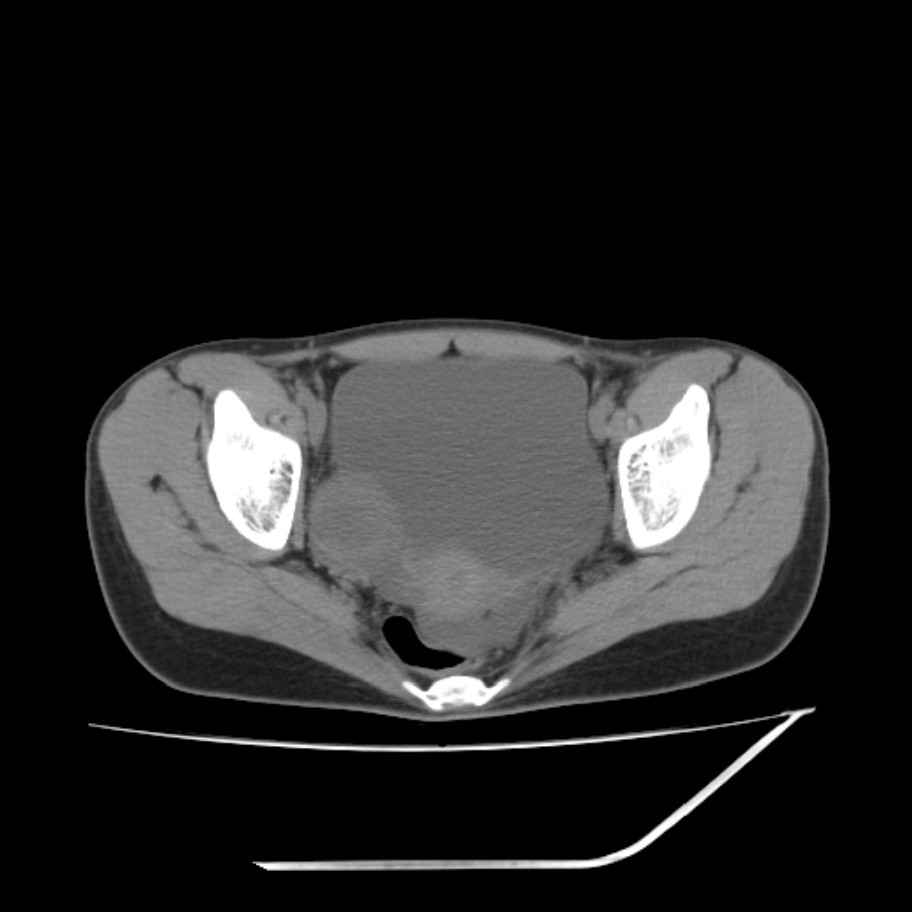

女,25岁。偶尔有右下腹不适感,余无明显异常。(结婚半年),囊壁较厚,是卵巢囊肿吗?

右侧卵巢区椭圆形囊性肿物,内壁光滑 无分隔。直肠子宫间隙内有少量积液征象。结合临床考虑卵巢巧克力囊肿,还要问问有没有痛经,本例ct怎么没有灌肠?要是灌肠或前一前口服造影剂,起码可以和肠管区别开

右侧囊性占位,1囊肿,2囊腺瘤。

考虑右侧卵巢囊性占位性病变(巧克力囊肿?),盆腔积液有不排除宫外孕可能,请结合临床和b超。

右侧卵巢囊伴盆腔少量积液。